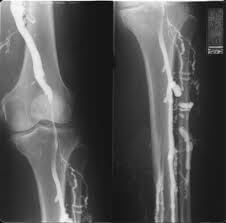

флебографический снимок при варикозе вен голени

Исследование вен нижних конечностей с контрастом показано при необходимости подтвердить диагноз, если с помощью функциональных проб и/или УЗИ сосудов получены сомнительные результаты. Обычно флебография используется нечасто, а только в случаях, которые действительно вызывают сомнения у врача в плане диагностики. Предполагаемые заболевания при этом таковы:

- Тромбоз глубоких вен голени и бедра,

- Варикозная болезнь нижних конечностей (комплексно оценивается функция клапанного аппарата поверхностных и глубоких вен),

- Врожденные аномалии строения венозных сосудов,

- Предполагаемое использование вены в качестве шунта, например, при аорто-коронарном шунтировании.